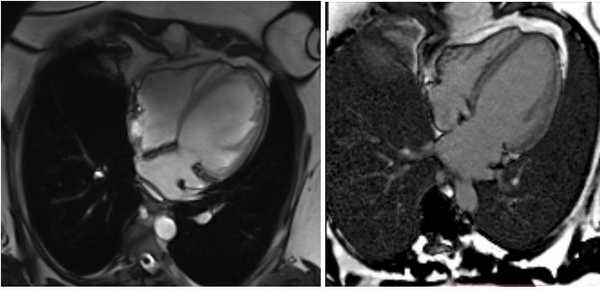

МРТ сердца. Расширение полости левого желудочка. Фиброзные изменения миокарда левого желудочка.

МРТ сердца. Расширение камер сердца. Поствоспалительный фиброз миокарда межжелудочковой перегородки.